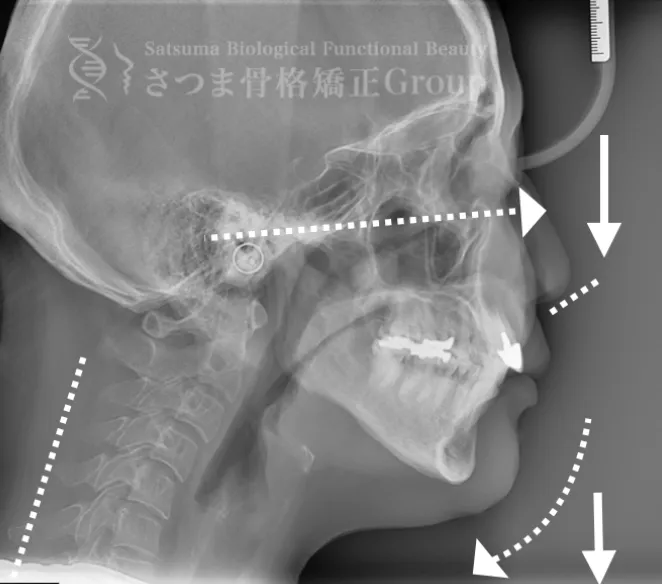

40代男性 F.K様 初回効果

下顎の後方回転あり。 中顔面が伸びて下方に落ちる。 中顔面の奥行きを失っている。 頚椎ストレートネック。 重度の首凝り

Posterior rotation of the mandible The midface is elongated and has dropped downward Loss of depth in the midface Cervical spine straightening (straight neck) Severe neck stiffness

AFTER(マウスピース使用時)

整骨後、形成したマウスピースで形と顎関節の前方回転を誘導。上部頸椎のリリースを促進し、自家矯正力が働きやすいように誘導。蝶形骨口蓋縫合と蝶形骨上顎縫合をモビライゼーションし、可動をブーストし中顔面を短縮。

重度の肩凝りも軽減

After the osteopathy, the custom-formed mouthpiece guides the shape and promotes forward rotation of the temporomandibular joint.

It facilitates the release of the upper cervical spine and encourages the body’s natural self-correcting ability.

Mobilization of the sphenopalatine suture and the sphenomaxillary suture boosts mobility and shortens the midface.